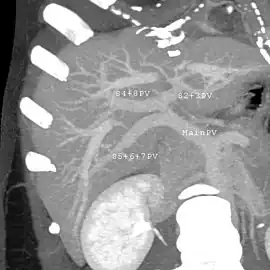

Axial CT image showing anomalous hepatic veins coursing on the liver's subcapsular anterior surface[74]

Maximum intensity projection (MIP) CT image as viewed anteriorly showing the anomalous hepatic veins coursing on the anterior surface of the liver

Lateral MIP view in the same patient as previous image